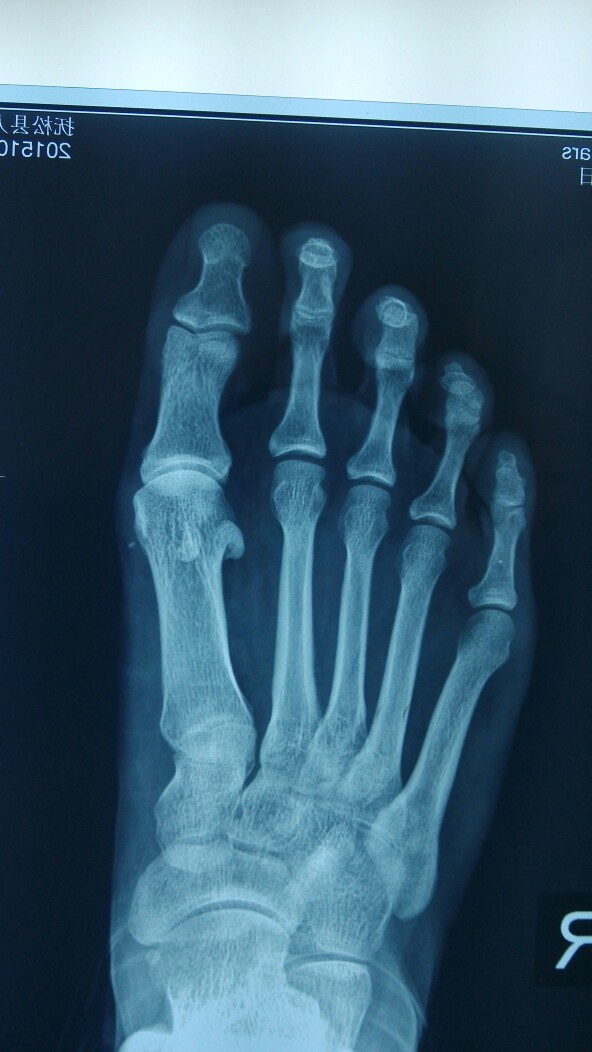

患者女,39岁,足底疼痛2年,一年前行足部鸡眼切除,疼痛无缓解。鸡眼复发。讨论下如何处理。